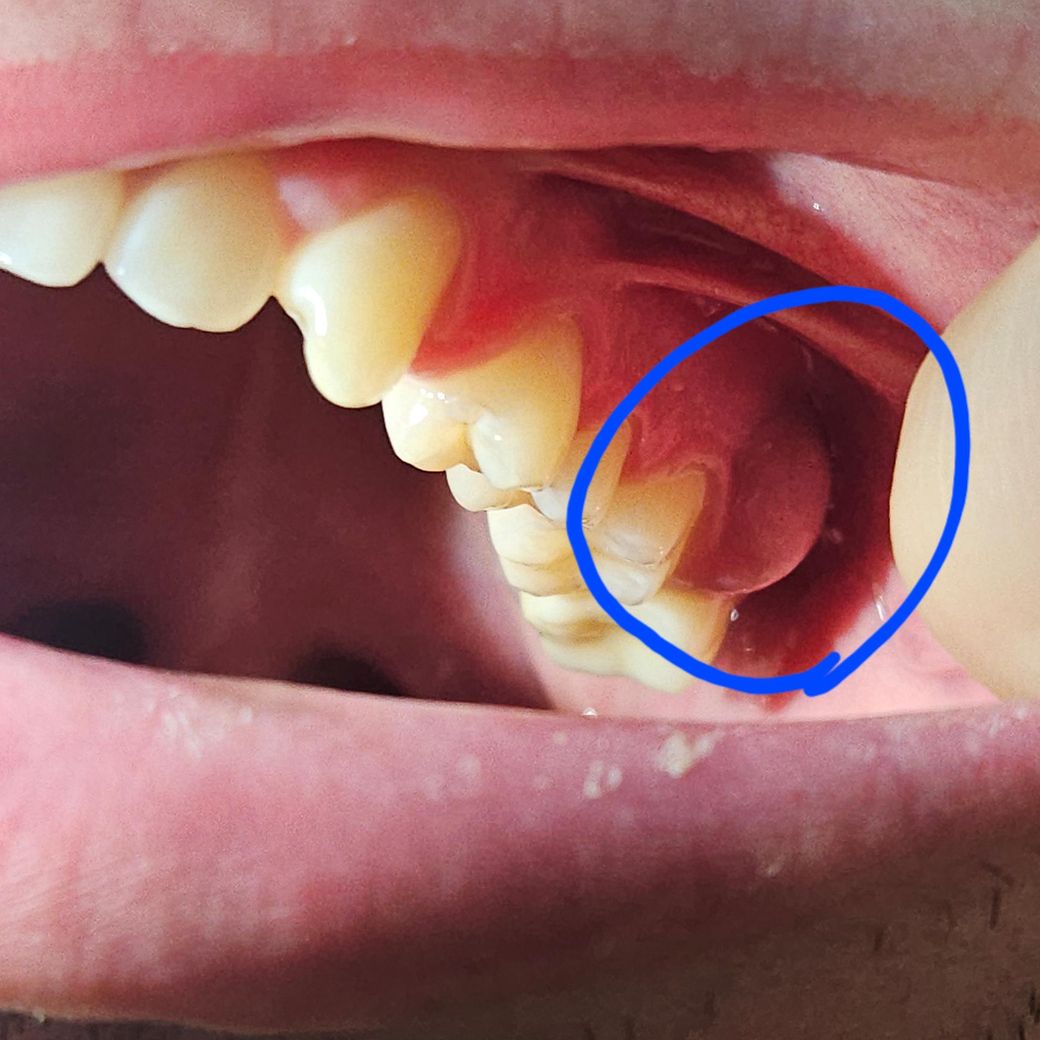

왼쪽 상단 사랑니 발치 후 앞쪽 어금니 잇몸 부음 및 통증

14일에 왼쪽 상단 사랑니 발치 후 사랑니 앞 어금니 쪽 잇몸이 붓고 통증이 심합니다.

입에 넣고 씹을때나 일상 생활 할 때도 잘때도 중간에 통증 때문에 잠에서 깹니다...

약간의 붓기가 있는 정도가 아니라 염증이 있을 가능성이 높아보이며 치과 가보셔야 할 것 같습니다.

저정도 부종이라면 잇몸에 농이 많이 차잇을것같습니다. 치과에 가셔서 사진을 찍어보시고 치료를 하시는게 좋을것같습니다.

사진으로 봤을 경우 잇몸이 부어 있는 부분은 사랑니와는 크게 연관이 없는 것으로 보입니다. 사랑니 앞에 있는 지하 주변에 염증이 생기면서 사진과 같이 부어 쓸 수 있습니다. 잇몸치료 등이 필요할 수 있을 것으로 생각됩니다.

자세한 확인을 위해서 치과에서 진료를 받아보는 것을 권유드립니다.

치과 가보시기 바랍니다 사랑니 발치 후 흔히 생기는 부종의 양상은 아닙니다 발치와 연관이 있을지 의문이고, 물혹의 양상입니다